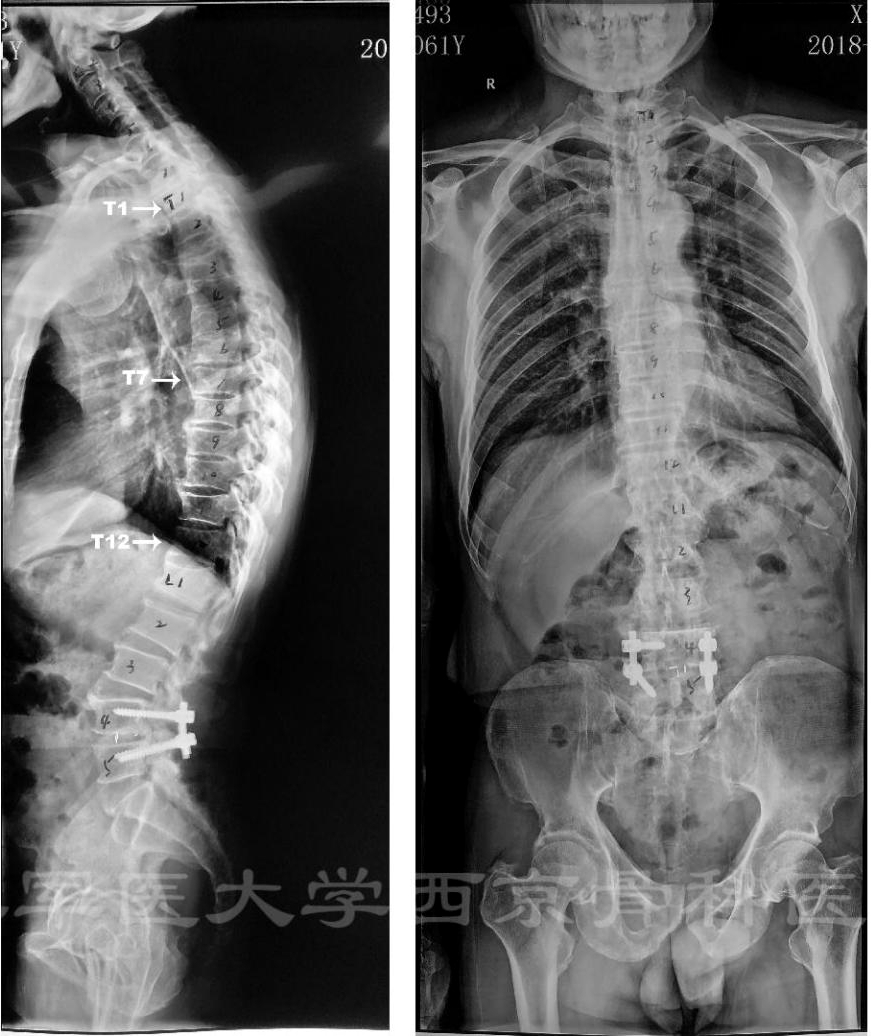

患者:男,61岁

主诉:双下肢麻木、无力11年,加重1月。

既往史:2003年行“颈后路单开门手术”;2010年行“胃癌根治术”;2013年行“腰椎手术”。

轮椅推入病房,脊柱活动度检查不能配合。剑突以下感觉减退。双下肢肌力Ⅱ~Ⅲ级。

诊断:胸椎管狭窄症

术前X线正侧位片